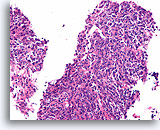

Invasief Ductaal carcinoom, Borst FNA, Celblok.

Met behulp van histologische coupes kunnen in sommige ductale carcinomen invasieve patronen geïdentificeerd worden [4]. Het invasieve patroon bestaat uit ductale cellen die binnen een actieve stroma groeien zonder lobulaire of ductale architectuur. De maligne cellen vertonen geen voorspelbare relatie met stromale referentiepunten en lijken het stroma onder willekeurige hoeken binnen te dringen. De kenmerken van invasiviteit worden in de volgende afbeeldingen geïllustreerd.

40X

Invasief Ductaal carcinoom, Borst FNA, Celblok.

Met behulp van histologische coupes kunnen in sommige ductale carcinomen invasieve patronen geïdentificeerd worden [4]. Het invasieve patroon bestaat uit ductale cellen die binnen een actieve stroma groeien zonder lobulaire of ductale architectuur. De maligne cellen vertonen geen voorspelbare relatie met stromale referentiepunten en lijken het stroma onder willekeurige hoeken binnen te dringen. De kenmerken van invasiviteit worden in de volgende afbeeldingen geïllustreerd.

40X

Ductaal carcinoom, Borst FNA, Celblok.

Let op de onregelmatige contour van de solide, smalle strengen met infiltratieve cellen (pijlen).

60X

Ductaal carcinoom, Borst FNA, Celblok.

Let op de onregelmatige contour van de solide, smalle strengen met infiltratieve cellen (pijlen).

60X